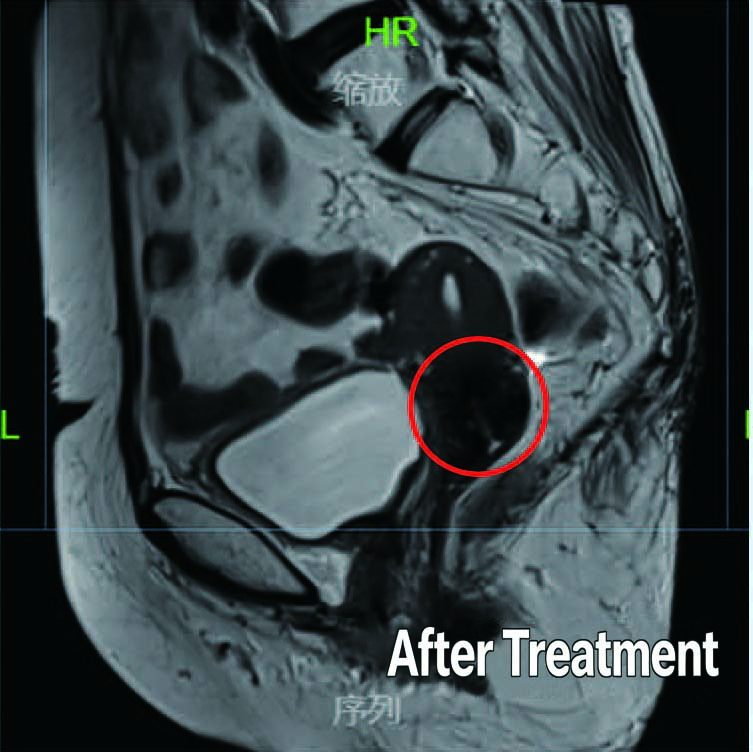

After Treatment

Patient: 73-year-old female

Diagnosis: Diagnosed Stage IIIA Cervical Cancer in February 2020

Treatment History: Patient underwent chemotherapy and interventional therapy at another hospital with unsatisfactory results.

Treatment at Our Hospital: Definitive radiotherapy for cervical cancer (External beam radiotherapy+ brachytherapy)

Outcome: Substantial reduction in tumor size noted post-treatment, with complete disappearance of the large tumor.